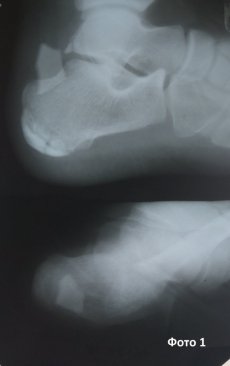

Під час медогляду у пацієнта виявили припухлість в ділянці стопи. Після проведеної рентгенографії знайшлиа загадкову скіалогічну структура. З анамнестичних даних медики з’ясували, що більше, ніж пів року тому чоловік зазнав поранення в ділянці цієї ж стопи склом, особливої уваги на яке пацієнт не звернув.

Після проведеного хірургічного втручання стороннє тіло успішно вилучено (фото 2,3). Медики підкреслюють, що не всі види скла є рентгенконтрастними. В даному випадку найймовірніше, що скло містило в своєму складі свинець тому і було виявлене на рентгенограмі.